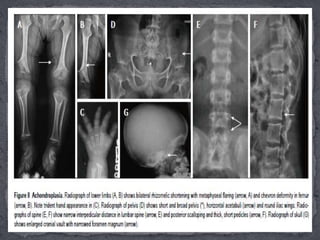

 Achondroplasia isthe most common non-lethal dysplasia and is the prototype of rhizomelic dwarfism.  It is inherited in an autosomal dominant fashion, with 80% occurring sporadically, attributable to spontaneous mutation on locus4p16.3 affecting Fibroblast Growth Factor Receptor 3(FGFR3) gene.  Age of manifestation: The typical features of achondroplasia are obvious at birth. The most characteristic changes are found in the spine, especially in the lumbar region, pelvis, limbs and skull.

Essential radiological features: (1)Symmetric shortening of all long bones, with proximal portions being more affected and lower limb involvement being more than the upper limb (rhizomelia). There’s relative flaring and splaying of metaphyses with normal epiphyses . (2) In children, the epiphysis is located closer to metaphyses leading to an apparent increase in the depth of the articular cartilage space. The two limbs of the V of metaphysis appear to embrace the epiphysis giving rise to a ball and socket relationship/chevron deformity . This appearance is more common at lower end of femur and tends to normalise with increasing age. (3) The hand bones appear thick and tubular with widely separated 2nd and 3rd digits of the hands and inability to approximate them in extension, leading to appearance of trident hand. (4) The pelvic cavity is short and broad, also called as champagne-glass appearance. There’s squaring of iliac wings with some roundening of corners on a frontal projection (elephant ear shaped iliac wings).

The inferior marginsof iliac wings and the roofs of acetabulum are flat and horizontal . The sacrosciatic notches are small with an exaggerated sacral tilt and large, anteriorly protruding sacral promontory; (5) In spine, there is progressive decrease in the interpedicular distance cranio-caudally in the lumbar spine, the decrease in distance becoming more conspicuous with age). Posterior scalloping of vertebral bodies is also common while anteriorly they may appear rounded giving rise to a bullet- shaped configuration. But the overall length of vertebral column and the vertebral heights are normal. There’s associated dorso-lumbar kyphoscoliosis in sitting position with exaggerated lumbar lordosis on standing up. Achondroplasts are prone for premature and severe spinal canal stenosis; (6) The skull shows narrowed skull base with narrowing of foramen magnum. There is compensatory over-expansion of the skull vault and frontal regions to accommodate the expanding brain. There’s relative mid- face hypoplasia and depressed nasal bones.